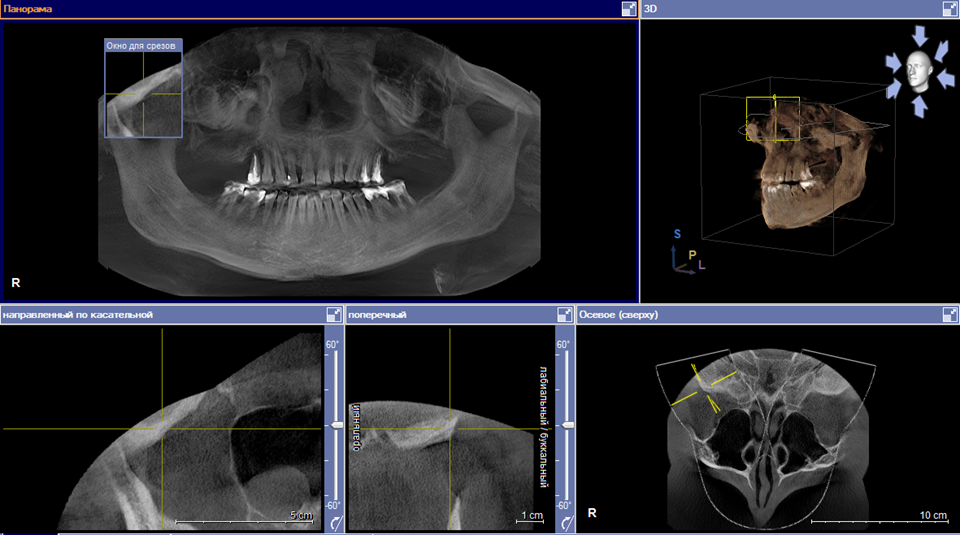

Chanba109 Опубликовано 26 марта, 2022 Поделиться Опубликовано 26 марта, 2022 Уважаемые специалисты, хочу поделиться своей ситуацией и спросить вашего совета. Ситуация следующая: мне 55 лет, до 2005 года терял зубы в верхней челюсти (был диагностирован парадонтоз, который сейчас стараюсь поддерживать в рамках). В 2005 году решил решить вопрос с восстановлением зубного ряда (съемным или несъемным). От имплантов отказался в пользу съемного протезирования из-за технических сложностей (тонкая кость верхней челюсти – требовался синус-лифтинг, снимок 2005 прилагаю) и общей высокой стоимости. Сделал выбор в пользу съемного гибкого нейлонового протеза Valplast, который ношу до настоящего времени, то есть уже 17 лет (фото протеза в настоящее время прилагаю). За это время никаких перебазировок, подгонок и т. п. с протезом не производилось, он сидит достаточно плотно, легко снимается и надевается, меня, в общем, полностью устраивал весь период использования. В настоящее время один из зубов (левая пятерка), за который держится протез, подлежит удалению (панорамный снимок, сделанный недавно, прилагаю). Встал вопрос о смене протеза или ином решении проблемы. У меня к вам следующие практические и теоретические, если так можно выразиться, вопросы: 1) Насколько критично идет уменьшение костной ткани в верхней челюсти? Насколько, по вашему мнению, этому способствовал гибкий нейлоновый протез или это, скорее, естественный процесс при парадонтозе? 2) Какой вариант протезирования с желательным бюджетом до 100 тыс. рублей (или немного выше) можете рекомендовать в моей ситуации? 3) Можете ли рекомендовать сделать еще один нейлоновый протез (или протез из аналогичных материалов - Acry Free или т. п.). 4) Надо ли перед протезированием удалять не только левую, но и правую пятерку (которая пока никак не беспокоит) или можно попробовать оставить ее? Панорамный_2005 год.tif Панорамный_2022 год.docx Ссылка на комментарий

Женька Опубликовано 26 марта, 2022 Поделиться Опубликовано 26 марта, 2022 Я бы убрал и слева и справа. Также обратить внимание на 1.2 зуб (боковой резец справа), возможно нужно полечить, под ОПТГ судить нельзя об этом. До 100 тысяч в нынешних реалиях это переделка протеза я думаю. Имплантация и синусы выйдут дороже. Касаемо первого вопроса опять же, по данным снимкам оценить это нельзя. Протез способствует в любом случае, но какая разница, если имплантация не вариант выбора для вас? Ссылка на комментарий

Chanba109 Опубликовано 28 марта, 2022 Автор Поделиться Опубликовано 28 марта, 2022 Спасибо за ответ. Имплантация в моем случае весьма небюджетна будет, это понятно. Но съемные протезы тоже разные бывают, какие можно рекомендовать при моем состоянии зубов и костной ткани (снимок МРТ 2022 года - выше в первом посте Евгения) ? Есть ли критические противопоказания к нейлоновому или т. п. гибкому протезу? Ссылка на комментарий